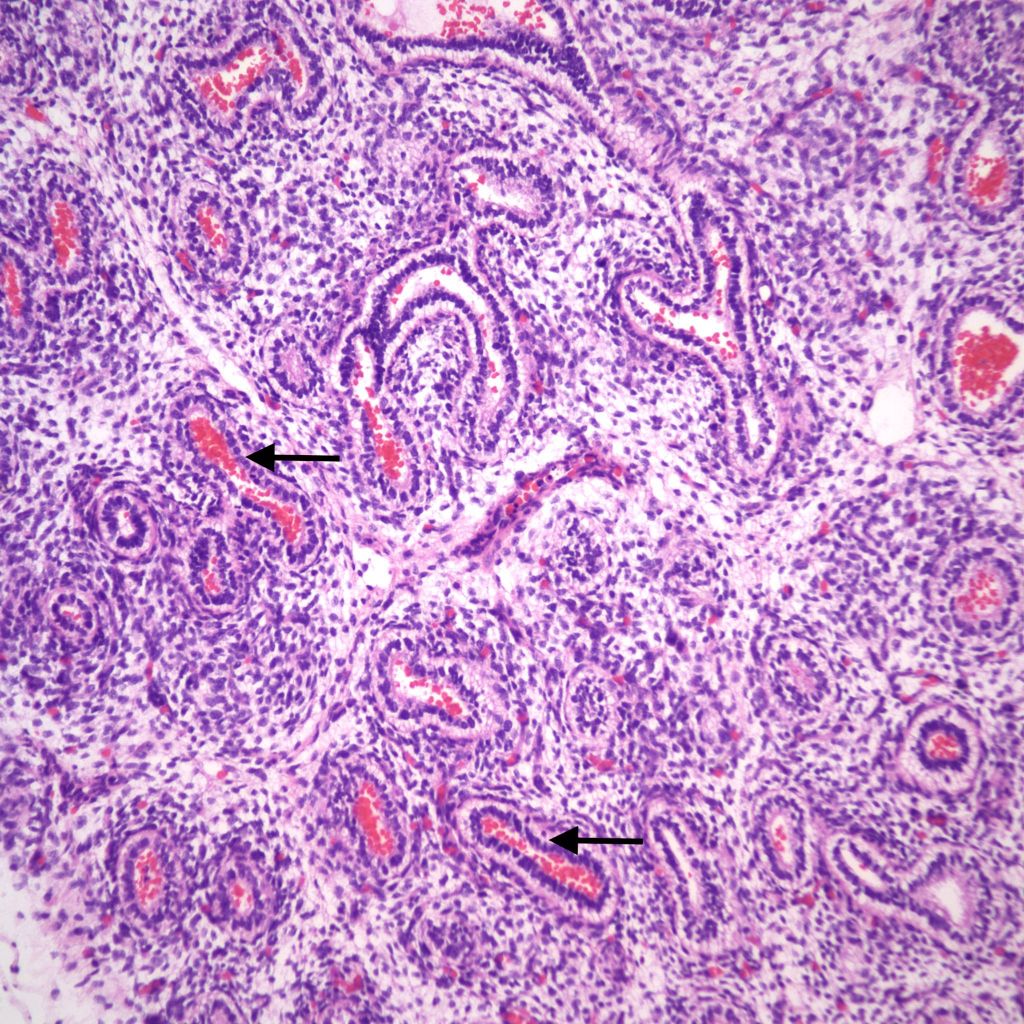

Infection: Even without gasping, microorganisms and neutrophils present in infected amniotic fluid would be able to traverse into the airways from normal, shallow respiration. This is also likely true for mobile neutrophils in the amniotic fluid. In previable fetuses, cuboidal cells lining the airways shed into the lumen and undergo karyorrhexis (apoptosis) that may resemble, but are morphologically distinct from neutrophils (fig 11a,b).

However, the karyorhectic cells lack the intact cytoplasm of neutrophils. It is not possible to observationally determine whether neutrophils in the airway are from aspiration of neutrophils in the amniotic fluid, or are from fetal neutrophils in response to aspirated bacteria. The exception is with focal bronchopneumonia which demonstrates a fetal inflammatory response with large, focal accumulations of neutrophils and vasodilatation of surrounding capillaries (fig 12a,b).

It is conceivable that bacteria can travel through the fetal airways after fetal death, but neutrophils in the lungs and gastrointestinal tract are presumed evidence of chorioamnionitis in the living fetus. Overgrowth of bacteria may be directly observable in the airways. Some organisms in stillbirth without postmortem retention, such as Group B beta hemolytic streptococcus show such overgrowth in the living fetus, while in other cases the bacterial overgrowth is likely postmortem (even if initially present in life), especially for organisms adapted to low environmental oxygen (Fig 13).